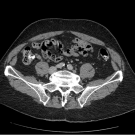

Tooba Sheikh, BS; Zafar Qureshi, MD; Austine Leleji, BSc, MD; Syed A.A. Rizvi, PhD, MBA

A 62-year-old woman with a past medical history of a retroperitoneal liposarcoma presented to our free health clinic following a recent emergency department (ED) discharge for a left lower extremity deep...